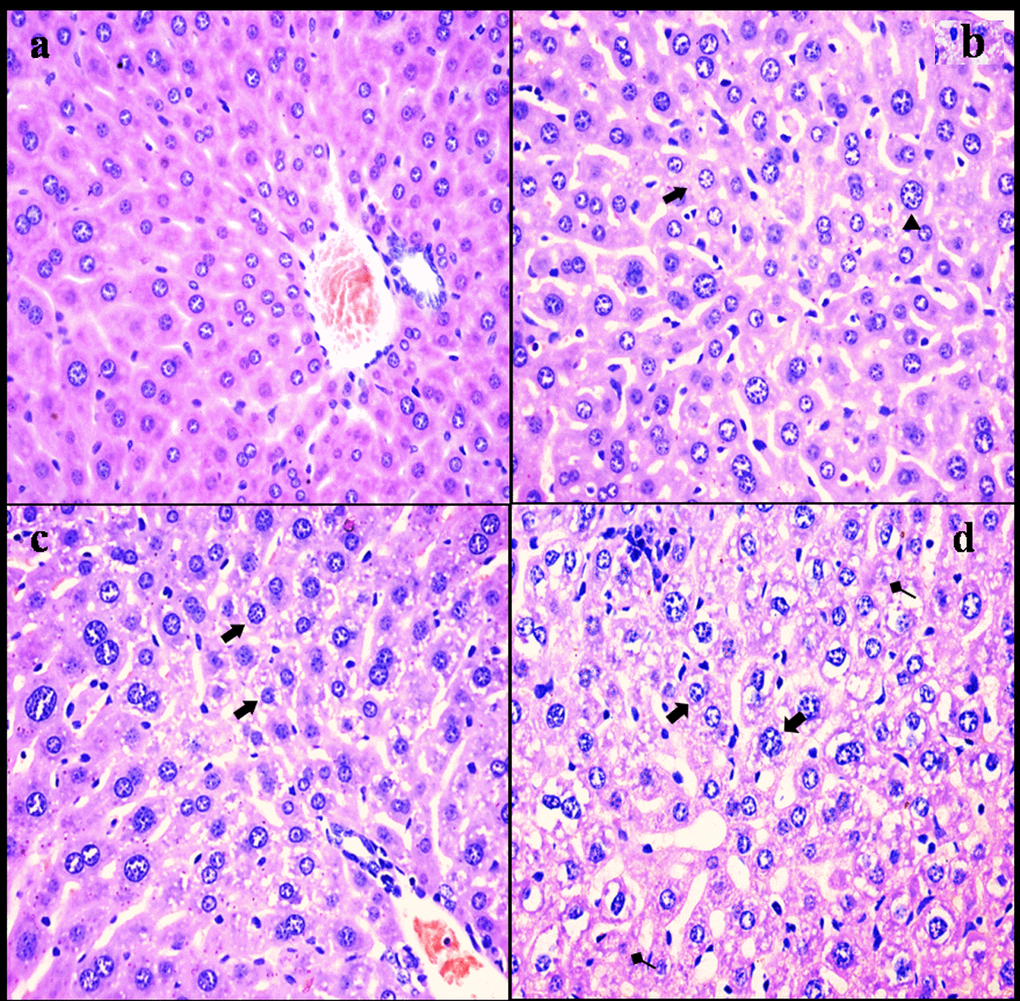

NaF resulted in histopathological lesions in a dose- and time-dependent manner. Lesions included hepatocellular granular degeneration, vacuolar degeneration and necrosis. In the granular and vacuolar degenerated hepatocytes, tiny particles and small or large vacuoles were appeared in the cytoplasm (Figure1). Karyorrhexis, karyolysis and hypochromatosis were appeared in the necrotic hepatocytes (Figure2). The above lesions were not observed in the control group.

Figure 1. Histopathological changes in the liver at 21 days of the experiment. (a) The control group (H&E × 400). (b) The 12 mg/kg group. Hepatocytes are swelled (Δ) and show slight granular and vacuolar degeneration (⇑, H&E ×400). (c) The 24 mg/kg group. Hepatocytes show granular and vacuolar degeneration (⇑, H&E × 400). (d) The 48 mg/kg group. Hepatocytes show obvious granular and vacuolar degeneration (⇑). Necrotic hepatic cells (↑) are observed (H&E × 400).